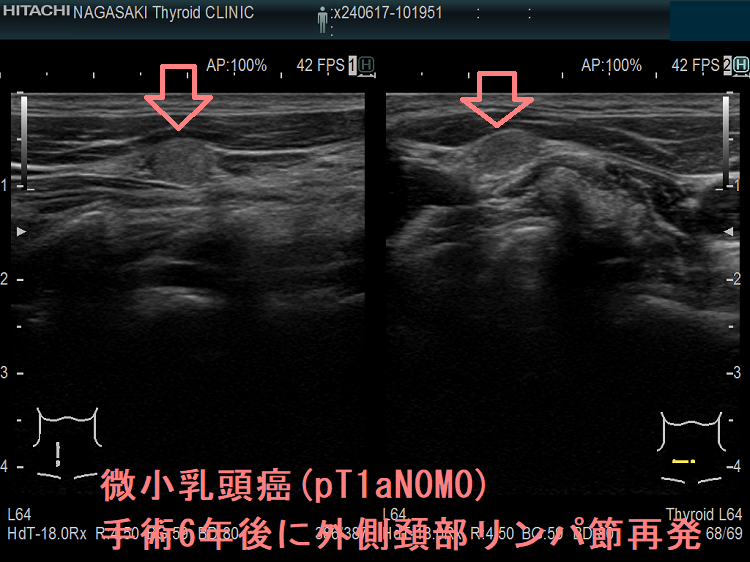

ケース①

ケース②